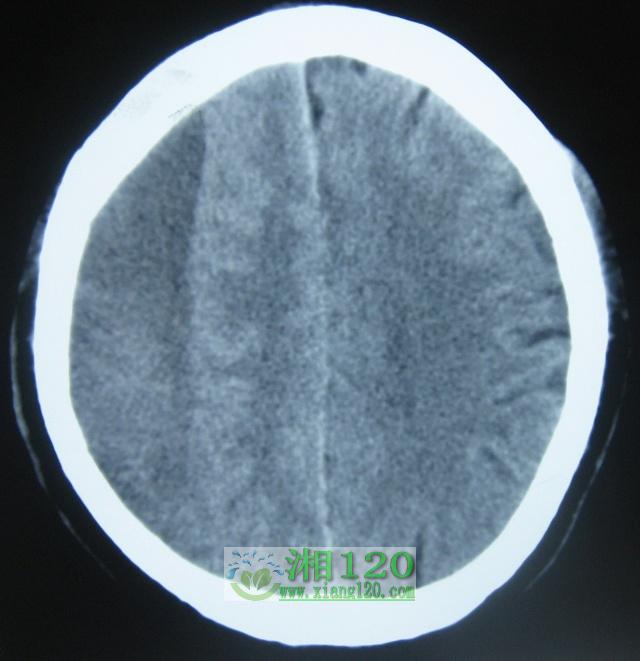

附图为其中一例患者的术前及术中图片。

术前头颅CT